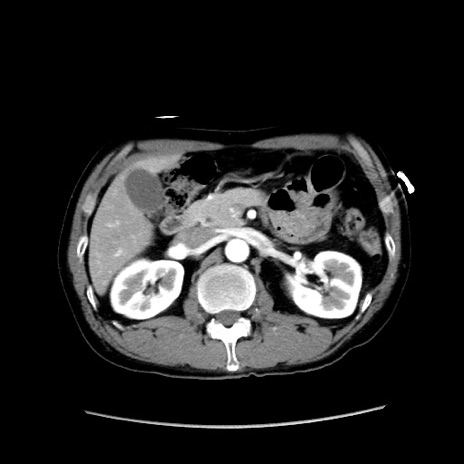

症例37(横断像)

【症例】40歳代 男性

【主訴】腹痛

【現病歴】4時間ほど前に電車に乗車中に臍部上より腹痛出現。徐々に増悪し起立困難となり、救急外来受診。生ものは数日食べていない。今朝お雑煮を食べた。

【身体所見】BT 36.8℃、BP 117/84mmHg、HR 91/min、SpO2 97%、苦悶様、腹部:臍上部広範囲圧痛あり、反跳痛±

【データ】WBC 8100、CRP 0.03